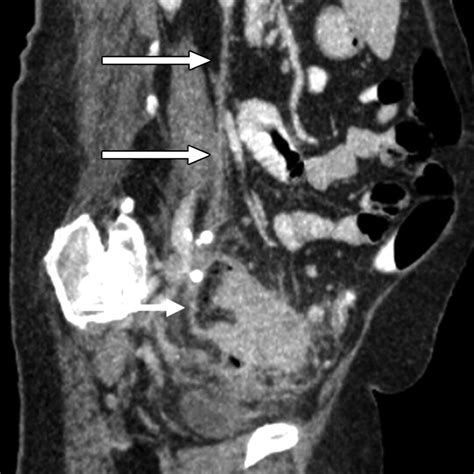

• Computed Tomography (CT) Scans: CT scans provide detailed images of the pelvic region and are highly effective in identifying phleboliths. They offer a three-dimensional view of the area, making it easier to locate and assess the deposits.

Case Study 1: A 45-year-old woman presented with chronic pelvic pain and was referred for a CT scan. The scan revealed multiple phleboliths in the pelvic veins. Further evaluation showed that she had pelvic congestion syndrome, a condition characterized by dilated and tortuous pelvic veins. Treatment with compression therapy and medications helped alleviate her symptoms.